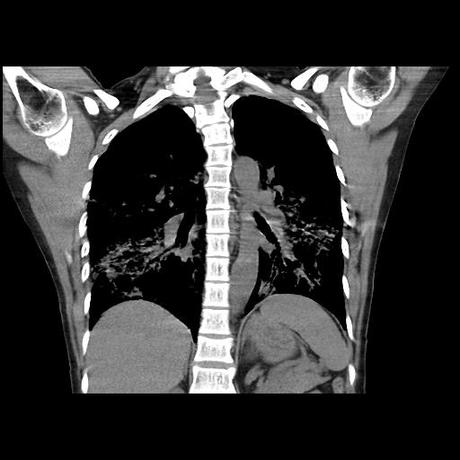

Se realiza volumen de tórax en fase simple, desde los opérculos torácicos hasta los hemidiafragmas, observándose:

El parénquima pulmonar con areas parcheadas difusas en vidrio despulido combinadas con otras areas hipodensas de baja atenuación debidas a atrapamiento aéreo y engrosamiento intersticial y zonas de fibrosis de predominio en lóbulos medios e inferiores de ambos pulmones.

- LOS HALLAZGOS PUEDEN ESTAR EN RELACIÓN A NEUMOPATIA INTERSTICIAL PROBABLE ETIOLOGIA HIPERSENSITIVA VS AUTOINMUNE/BACTERIANA/FUNGICA.